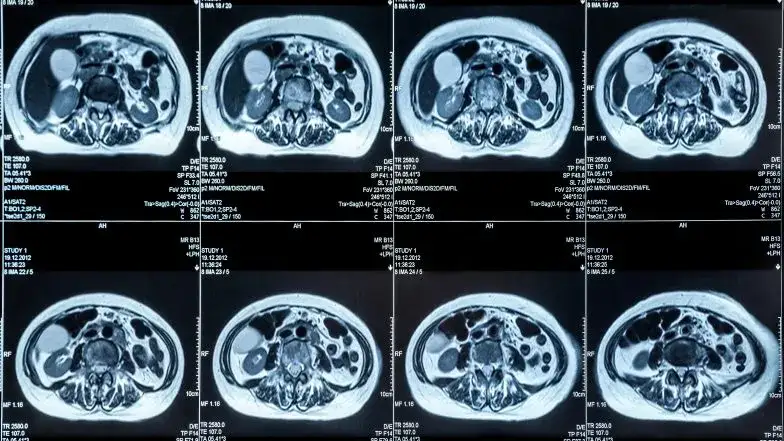

Wielofazowa tomografia komputerowa (TK)

To badanie jest "złotym standardem" w diagnostyce raka trzustki. Wykonuje się je z podaniem kontrastu dożylnego w kilku fazach, co pozwala na bardzo dokładne zobrazowanie trzustki, naczyń krwionośnych w jej okolicy oraz sąsiednich narządów. TK umożliwia precyzyjne określenie lokalizacji guza, jego wielkości, naciekania na okoliczne struktury (co jest kluczowe dla oceny operacyjności) oraz wykrycie ewentualnych przerzutów do węzłów chłonnych czy innych narządów.

Rezonans magnetyczny (MRI)

Rezonans magnetyczny ma czułość porównywalną z tomografią komputerową i jest szczególnie przydatny w kilku sytuacjach. Jest to badanie bez użycia promieniowania rentgenowskiego, co jest ważne dla niektórych pacjentów. MRI jest niezastąpione w ocenie dróg żółciowych i przewodu trzustkowego (w technice MRCP cholangiopankreatografii rezonansu magnetycznego), co pozwala wykryć zwężenia czy poszerzenia tych struktur. Jest również preferowane u pacjentów z alergią na kontrast jodowy, stosowany w TK.